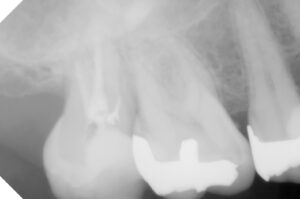

冠を被せた第二大臼歯の問題以上に、痛みは

第一大臼歯の詰め物の下が虫歯になっている

ことを説明し、処置内容と概算費用をつたえ

レントゲンでは神経の詰め物の状態の違い→

歯根の崩壊度は経時的なもの?→